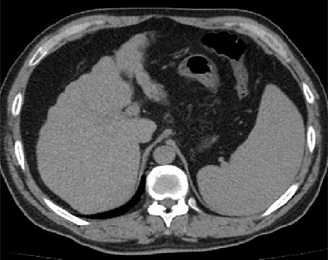

Developing a scoring system for staging patients with hepatic colorectal metastases is important for prognosis and for identifying those who will benefit from additional systemic therapy.

Due to advances in chemotherapy, biologic therapy, and the development of liver-oriented treatment options, the survival of patients with metastatic cancer has more than doubled, and increasing numbers of patients have been cured, even among those with advanced disease.

This article will review the current practice of hepatic resection for colorectal liver metastases, including the possibility of combined resection of hepatic metastases at the time of resection of the primary cancer.